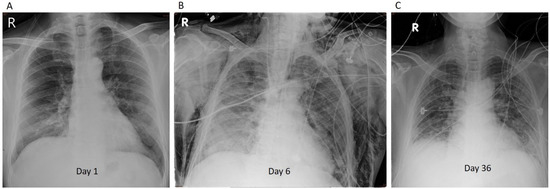

A 61-year-old man with a history of hypertension and type 2 diabetes mellitus presented to the emergency department (ED) with progressive dyspnea on exertion and hypoxia, having been under hotel quarantine. His oxygen saturation in room air was 85%. In the ED, bilateral opacities on chest radiography (Figure 1A) and symptom progression were observed. The test for COVID-19 was positive with an Xpert E gene cycle threshold value of 26.8. A non-rebreathing mask (15 L/min) was used to maintain oxygen saturation > 94%. Physical examination was significant for bilateral rales on auscultation of the lungs. On admission, intravenous ceftaroline and oral azithromycin were administered, along with remdesivir, dexamethasone, and tocilizumab (280 mg, 4 mg/kg (lower dose due to elevated liver enzymes)). The patient was transferred to the ICU with progressive hypoxemia (oxygen saturation 91% under a non-rebreathing mask (15 L/min)). He received high-flow nasal cannula (HFNC) and was switched to piperacillin–tazobactam and levofloxacin 3 days after admission to the ICU. The patient responded poorly to HFNC and was soon placed in the prone position. On Day 6, intubation with mechanical ventilation was performed for hypoxia, and the second dose of tocilizumab (4 mg/kg) was administered for suspected cytokine release syndrome (CRS) based on increased inflammatory markers [6] (lactate dehydrogenase (LDH): 418 IU/L; D-dimer: 809 ng/mL). Chest radiography revealed bilateral lung infiltration, indicating rapidly progressive diffuse pulmonary edema (Figure 1B).

Figure 1. Representative case 1 (Patient 3): (A) Bilateral opacities on chest radiography taken in the emergency department. (B) Chest radiography revealed bilateral lung infiltration, indicating rapidly progressive diffuse pulmonary edema.

On Day 7, positive end-expiratory pressure increased to 12 mmHg, with a fraction of inspired oxygen (FiO2) of >75% required to maintain oxygen saturation > 90%. The patient was placed in the prone position for 97 h. The blood Aspergillus antigen (galactomannan) titer on Day 15 was 0.73. The antifungal agent micafungin, used since Day 13, was switched to intravenous voriconazole [7]. Oxygenation and chest radiography improved, and the patient was extubated on Day 18. HFNC was well tolerated after extubation. The patient was transferred to the general ward for further treatment for ventilator-associated pneumonia. On Day 18, his sputum culture was positive for Burkholderia cenocepacia. Antibiotics and antifungal agents were discontinued 10 days later. The patient was discharged on Day 28.